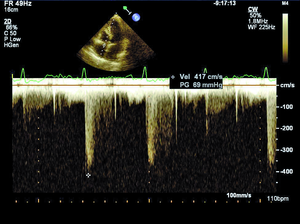

Rycina 1. Nieznacznie podwyższony gradient niedomykalności trójdzielnej (TRPG) 35 mm Hg mierzony w spoczynku u chorej z SSc.

Według najnowszych zaleceń Europejskiego Towarzystwa Kardiologicznego nadciśnienie płucne (pulmonary hypertension, PH) rozpoznajemy, gdy średnie ciśnienie w tętnicy płucnej (mPAP) w spoczynku oznaczane w pomiarze bezpośrednim podczas cewnikowania prawego serca (right heart catetherization, RHC) wynosi ≥25 mm Hg (przy normie do 20 mm Hg) [8]. W zależności od zastosowanych metod diagnostycznych, kryteriów rozpoznania oraz badanej populacji PH rozpoznaje się u 5-50% chorych z SSc [9]. Tętnicze nadciśnienie płucne występuje zwykle u chorych z lSSc i jest stwierdzane u ok. 7-12% pacjentów [8]. Śródmiąższowa choroba płuc obserwowana jest częściej w dSSc i jest przyczyną PH wtórnego do zajęcia płuc i hipoksemii [10]. W przebiegu sklerodermii może również rozwinąć się żylne PH oraz sporadycznie przewlekłe zakrzepowo-zatorowe nadciśnienie płucne (chronic thromboembolic pulmonary hypertension, CTEPH) [8,11]. W przypadku podejrzenia PH wymagana jest szybka i precyzyjna diagnostyka, ponieważ wczesne postawienie właściwego rozpoznania pozwala na włączenie celowanego leczenia poprawiającego rokowanie w tej grupie chorych. Podczas diagnostyki PH koniecznie należy również ustalić, jaki mechanizm jest odpowiedzialny za jego rozwój, ponieważ to determinuje dalsze postępowanie. Echokardiografia przezklatkowa jako metoda nieinwazyjna i łatwo dostępna jest badaniem przesiewowym w diagnostyce PH, a także służy do monitorowania postępu choroby u pacjentów z już rozpoznanym nadciśnieniem płucnym. Według wytycznych europejskich zalecane jest wykonywanie badania echokardiograficznego raz w roku u objawowych pacjentów z SSc (klasa zaleceń I, poziom dowodów A) oraz rozważenie wykonania takiego badania u chorych bez objawów (IIb/C) [8]. Podejrzenie PH w ocenie echokardiograficznej wysuwa się, gdy skurczowe ciśnienie w tętnicy płucnej (right ventricular systolic pressure, RVSP) wynosi >36 mm Hg, co odpowiada prędkości fali niedomykalności trójdzielnej >2,8 m/s lub gdy stwierdza się inne odchylenia echokardiograficzne, wskazujące na PH przy prawidłowym RVSP [8]. Należy jednak pamiętać, że echokardiografia w diagnostyce PH wciąż pozostaje metodą przesiewową, a złotym standardem nadal jest RHC [8]. W ostatnich latach za pomocą echokardiografii wykazano, że u chorych z SSc dochodzi do nadmiernego wzrostu ciśnienia w tętnicy płucnej podczas wysiłku (ryc. 1, 2) [12]. U zdrowych osób ciśnienie w tętnicy płucnej podczas wysiłku fizycznego pozostaje niezmienione lub wzrasta tylko nieznacznie. Znaczenie tego zjawiska nie zostało w pełni poznane. Można podejrzewać, że u pacjentów z SSc i prawidłowym spoczynkowym ciśnieniem w tętnicy płucnej indukowany wysiłkiem fizycznym nadmierny wzrost ciśnienia w tętnicy płucnej jest wczesnym objawem waskulopatii tętniczek płucnych. Możliwe, że chorzy ci są w przedklinicznym stadium PAH związanego z SSc i mogliby w przyszłości skorzystać z wcześniejszego włączenia leczenia celowanego na tętniczki płucne. Innym potencjalnym mechanizmem rozwoju spoczynkowego PH lub nieprawidłowego wzrostu ciśnienia w tętnicy płucnej podczas wysiłku jest dysfunkcja rozkurczowa lewej komory (left ventricle, LV). Postępujące włóknienie mięśnia serca powoduje upośledzenie relaksacji LV, co w warunkach obciążenia wysiłkiem powoduje nadmierny wzrost pozawłośniczkowego ciśnienia w tętnicy płucnej. Ta interesująca hipoteza jest poparta coraz większą liczbą badań prowadzonych w ostatnich latach [11,13]. W badaniach własnych w grupie 85 pacjentów z SSc autorzy wykazali nadmierny wysiłkowy wzrost pozawłośniczkowego ciśnienia w tętnicy płucnej u 15 (75%) z 20 chorych poddanych spoczynkowemu i wysiłkowemu RHC. Identyfikacja grupy chorych z SSc i nieprawidłowym wzrostem ciśnienia w tętnicy płucnej o etiologii żylnej jest bardzo ważna ze względu na potencjalne wczesne możliwości terapeutyczne w tej grupie pacjentów. Niewątpliwie zagadnienie nadmiernego wzrostu ciśnienia w tętnicy płucnej podczas wysiłku, jego etiologii oraz roli echokardiografii wysiłkowej w diagnostyce PH wymaga dalszych badań.